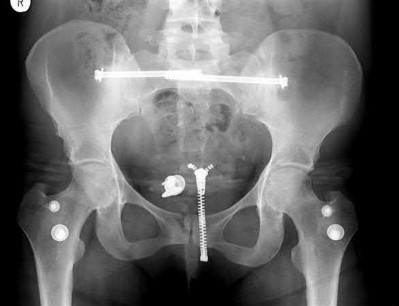

A 35 year-old female presents after prolonged extrication from a motor vehicle collision complaining of severe pelvic pain. Physical examination reveals diminished perianal sensation. She is otherwise neurologically intact. Figures A through D are radiographs and representative CT cuts of her injury. Which of the following nerve roots has likely been injured by the acute trauma?

The clinical scenario is consistent with a high-energy sacral fracture. The radiographs in figures A and B demonstrate a sacral fracture with posterior displacement of the right hemipelvis seen on the inlet view. Figures C and D are axial and sagittal CT images which show a displaced fracture of the right

hemisacrum along with a transvere fracture component through the S3 body . Diminished perianal sensation is concerning for an S2 nerve root injury.

Mehta et al reviewed the current management of sacral fractures. They note that the S1 and S2 nerve roots are more likely to be injured with sacral fractures as they occupy 1/3 to 1/4 of the neural foramina, as opposed to S3 and S4, which only occupy 1/6 of the neural foramina.

Robles reviewed the current literature to ascertain principles of evaluation and treatment for transverse sacral fractures. The author notes that injury to nerve roots S2 to S5 is manifested by impairment of urinary and anal continence and sexual function.